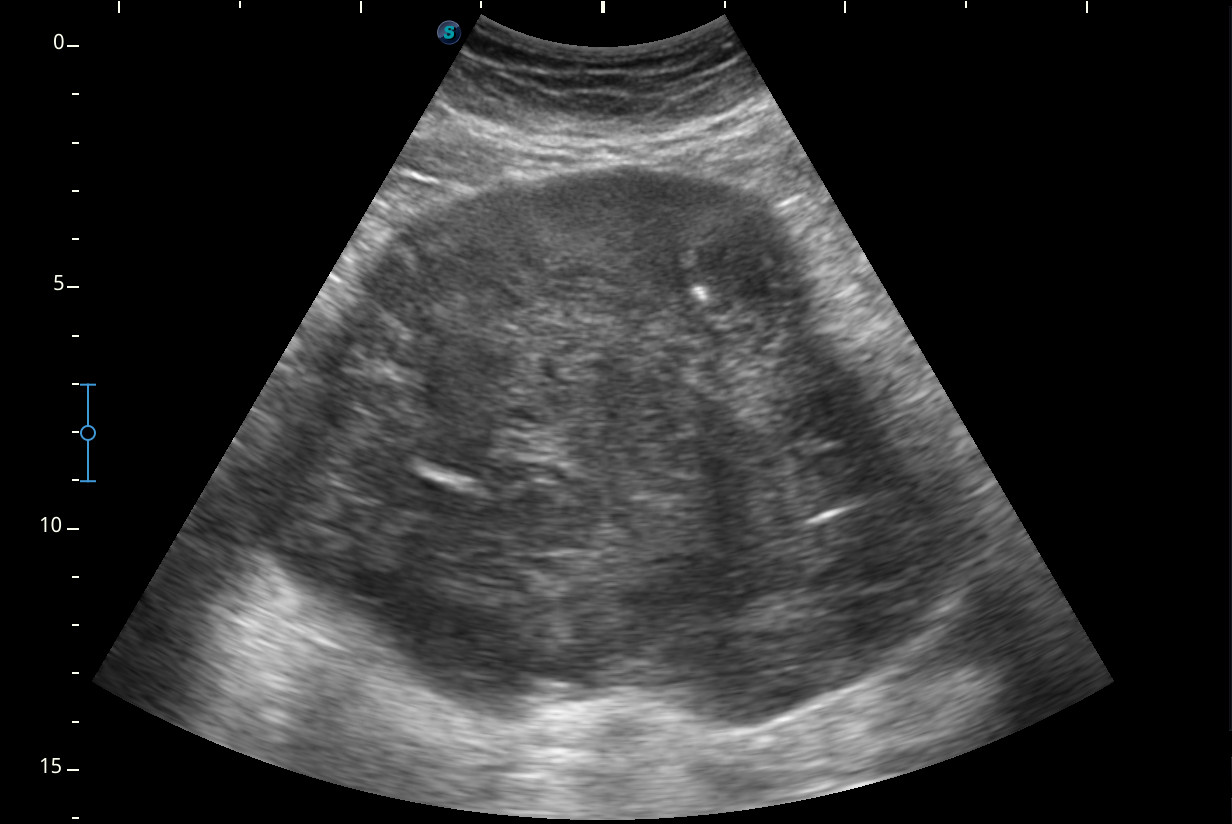

Hallazgos ecográficos

Se visualiza una masa heterogénea de unos 10 x 13 cm aproximadamente de diámetro con posibles focos necróticos y captación Doppler color, de dudosa organodependencia, que podría corresponder a un sarcoma retroperitoneal.